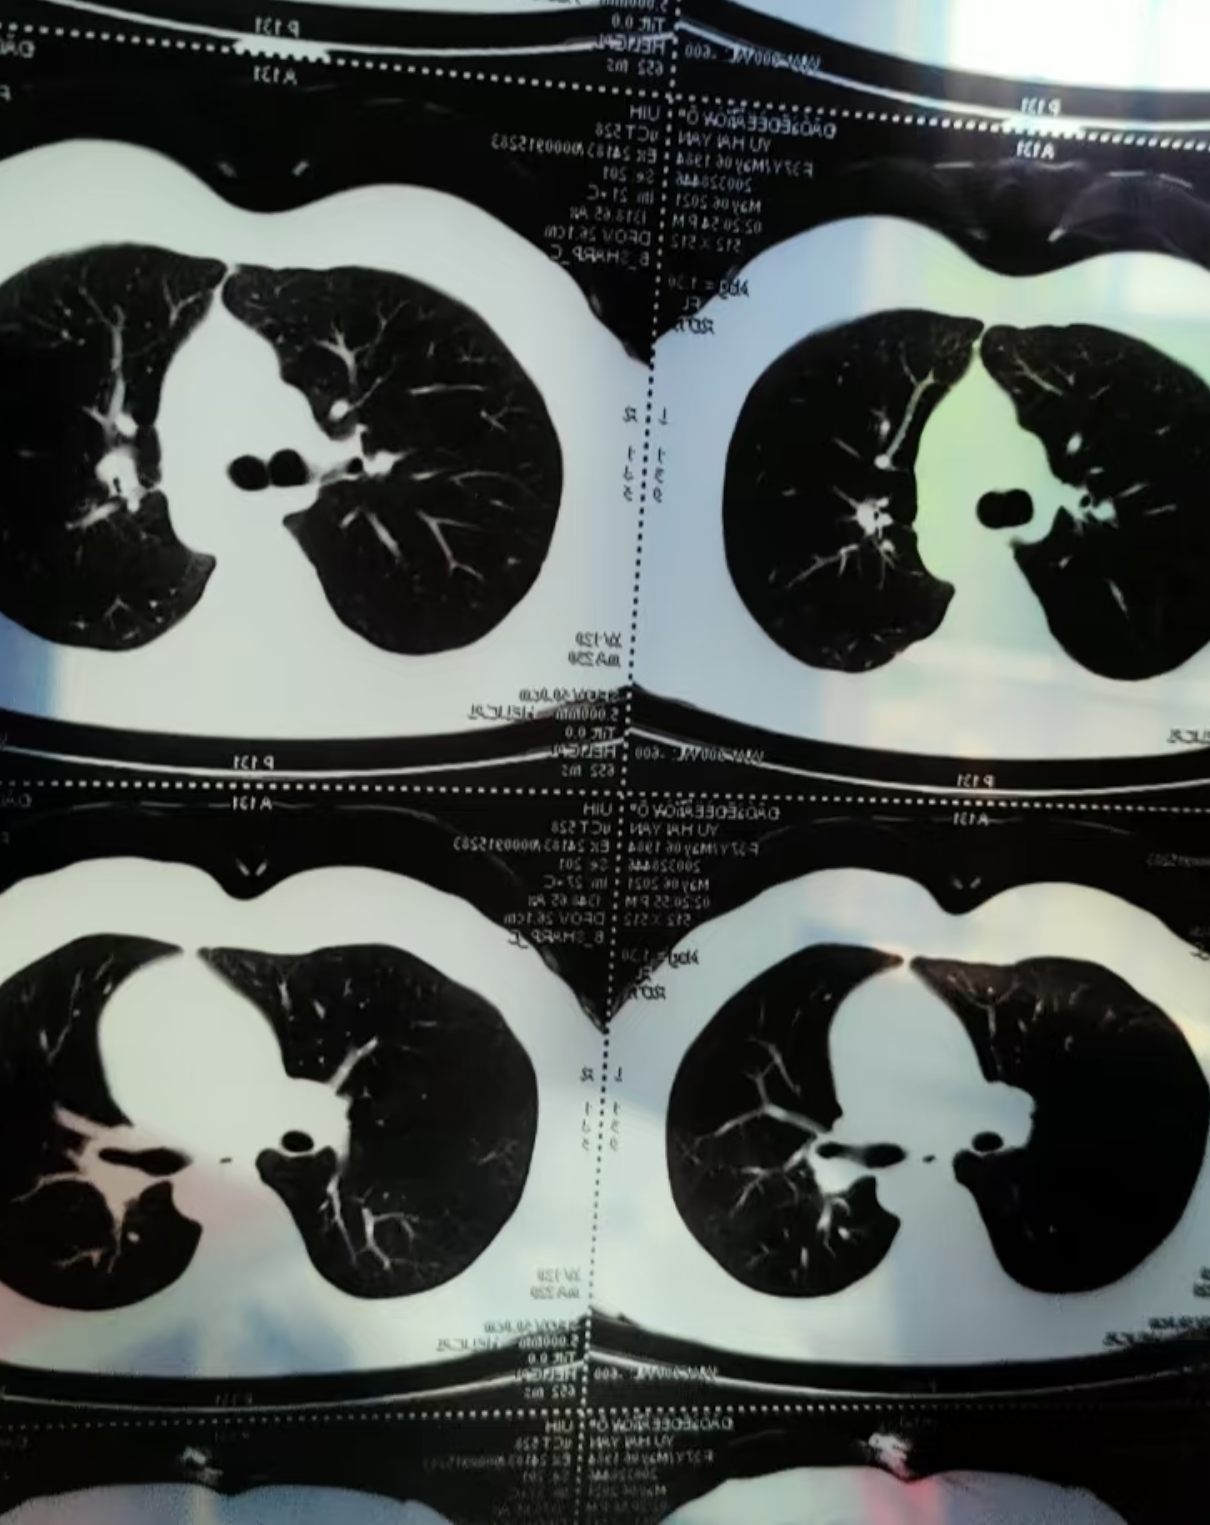

肺结节是通过肺部影像学检查发现的直径小于等于3cm的类圆形或不规则形病灶,其严重程度需结合病因治疗时机综合判断病因与严重性关联肺结节本身无传染性,多数患者无症状,常在体检时偶然发现其严重性主要取决于病因1若由肺部真菌感染肺腺瘤样增生肺错构瘤等良性病变引起,及时治疗如抗真菌药。

肺部结节的严重程度需综合判断,不能一概而论,其严重性主要与结节特征及患者高危因素相关结节大小是关键指标小于5毫米的结节多为良性,通常建议定期复查胸部CT如每612个月一次以监测变化若结节大于8毫米,尤其是短期内明显增大,或直径超过15毫米,恶性风险显著升高,需进一步检查形态与影像。

肺上2cm的结节是否严重不能一概而论,需结合结节特征患者病史及身体状况综合判断结节特征方面2cm的结节属于较大结节,恶性可能性相对较高若结节形状不规则边缘不清晰或有分叶,或为实性结节或部分实性结节含磨玻璃成分,需高度警惕恶性可能此外,倍增时间结节增长速度也是评估性质的。

肺部结节的严重程度需综合评估,多数情况下不严重,但需警惕恶性可能具体判断需结合以下因素结节大小直径小于5毫米的微小结节多为良性,尤其是首次发现且无高危因素者,通常建议定期复查如每612个月一次若结节直径超过8毫米,尤其是持续增大者,恶性风险显著升高,需进一步检查形态特征边缘。

多数肺部结节为良性病变,常见原因包括炎症结核或肉芽肿等这类结节通常体积较小,边缘光滑,无显著症状,一般不严重医生通常会建议定期复查CT,动态观察结节是否缩小消失或保持稳定,以排除恶性可能若结节存在以下特征,需警惕恶性可能结节体积较大直径超过8毫米的结节恶性风险显著升高形态不。

肺部结节的严重程度需综合评估,不能简单判定结节大小是初步判断的关键指标直径小于5毫米的结节多为良性,恶性概率较低,病情相对不严重,通常建议定期复查如每612个月进行一次胸部CT以观察变化直径在510毫米的结节,恶性风险有所增加,需结合其他特征进一步评估,可能需进行增强CT或PETCT检查。

肺部微小结节的严重性不能一概而论,需结合以下因素综合判断1 结节大小直径小于5毫米的结节定义为微小结节,通常恶性可能性较低,但需定期复查如首次检查后3个月6个月12个月复查观察变化若结节直径超过10毫米,恶性风险显著增加,需进一步检查2 结节形态良性结节多表现为边缘光滑规则。